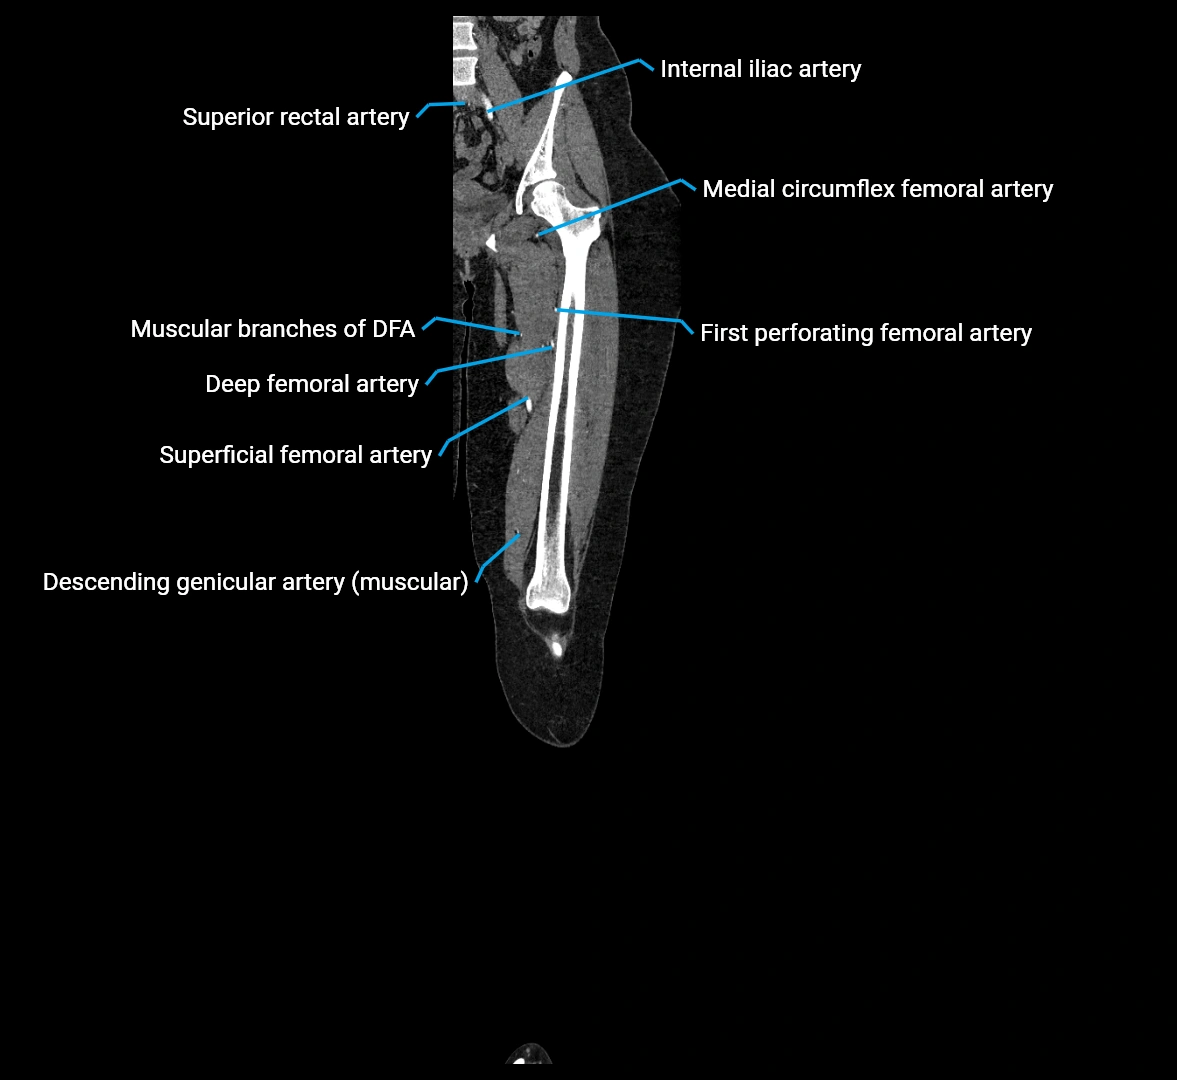

Contrast-enhanced CT (CTA):

• Gold standard for abdominal aortic imaging

• Provides excellent detail of lumen, wall, aneurysm, thrombus, and branch vessels

• Multiplanar and 3D reconstructions help in aneurysm measurement, stent graft planning, and dissection evaluation

• Detects acute rupture, traumatic injury, or occlusion with high sensitivity